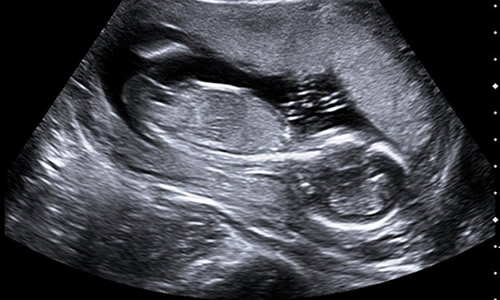

Hamilelik döneminde bebeğin eşi olarak tabir edilen plasenta rahmin herhangi bir yerine yerleşebilir. Rahim bölgesinin ön tarafında, arka duvarına ya da rahim kubbesi olarak adlandırılan bölgeye yerleşebilir. Tüm bunlarla beraber plasentanın aşağı bölgeye yani rahim ağzına yarın olan bölgeye yerleşmesi de sık rastlanan durumlar arasında yer alıyor. Bu durumda halk arasında plasentanın aşağıda olması ya da plasentanın önde olması olarak adlandırılır.

Bazı durumlarda plasenta doğum yaklaştıkça hafif yukarıya doğru çıkabiliyor. Genellikle plasentanın önde olması durumunda hekimler sıklıkla ultrason muayenesi ile yerini takibe alır. Eğer anne adayının rahim ağzı kısa ise bu durumda erken doğum riski ortaya çıkabiliyor. Erken doğum riskinden söz etmemek için rahim ağzının 3 cm’den daha uzun olması gerekiyor. Aktivite kısıtlamaları ve yorgunluktan kaçınma gibi durumlarda herhangi bir sorun olmadan normal doğum yapılabiliyor.